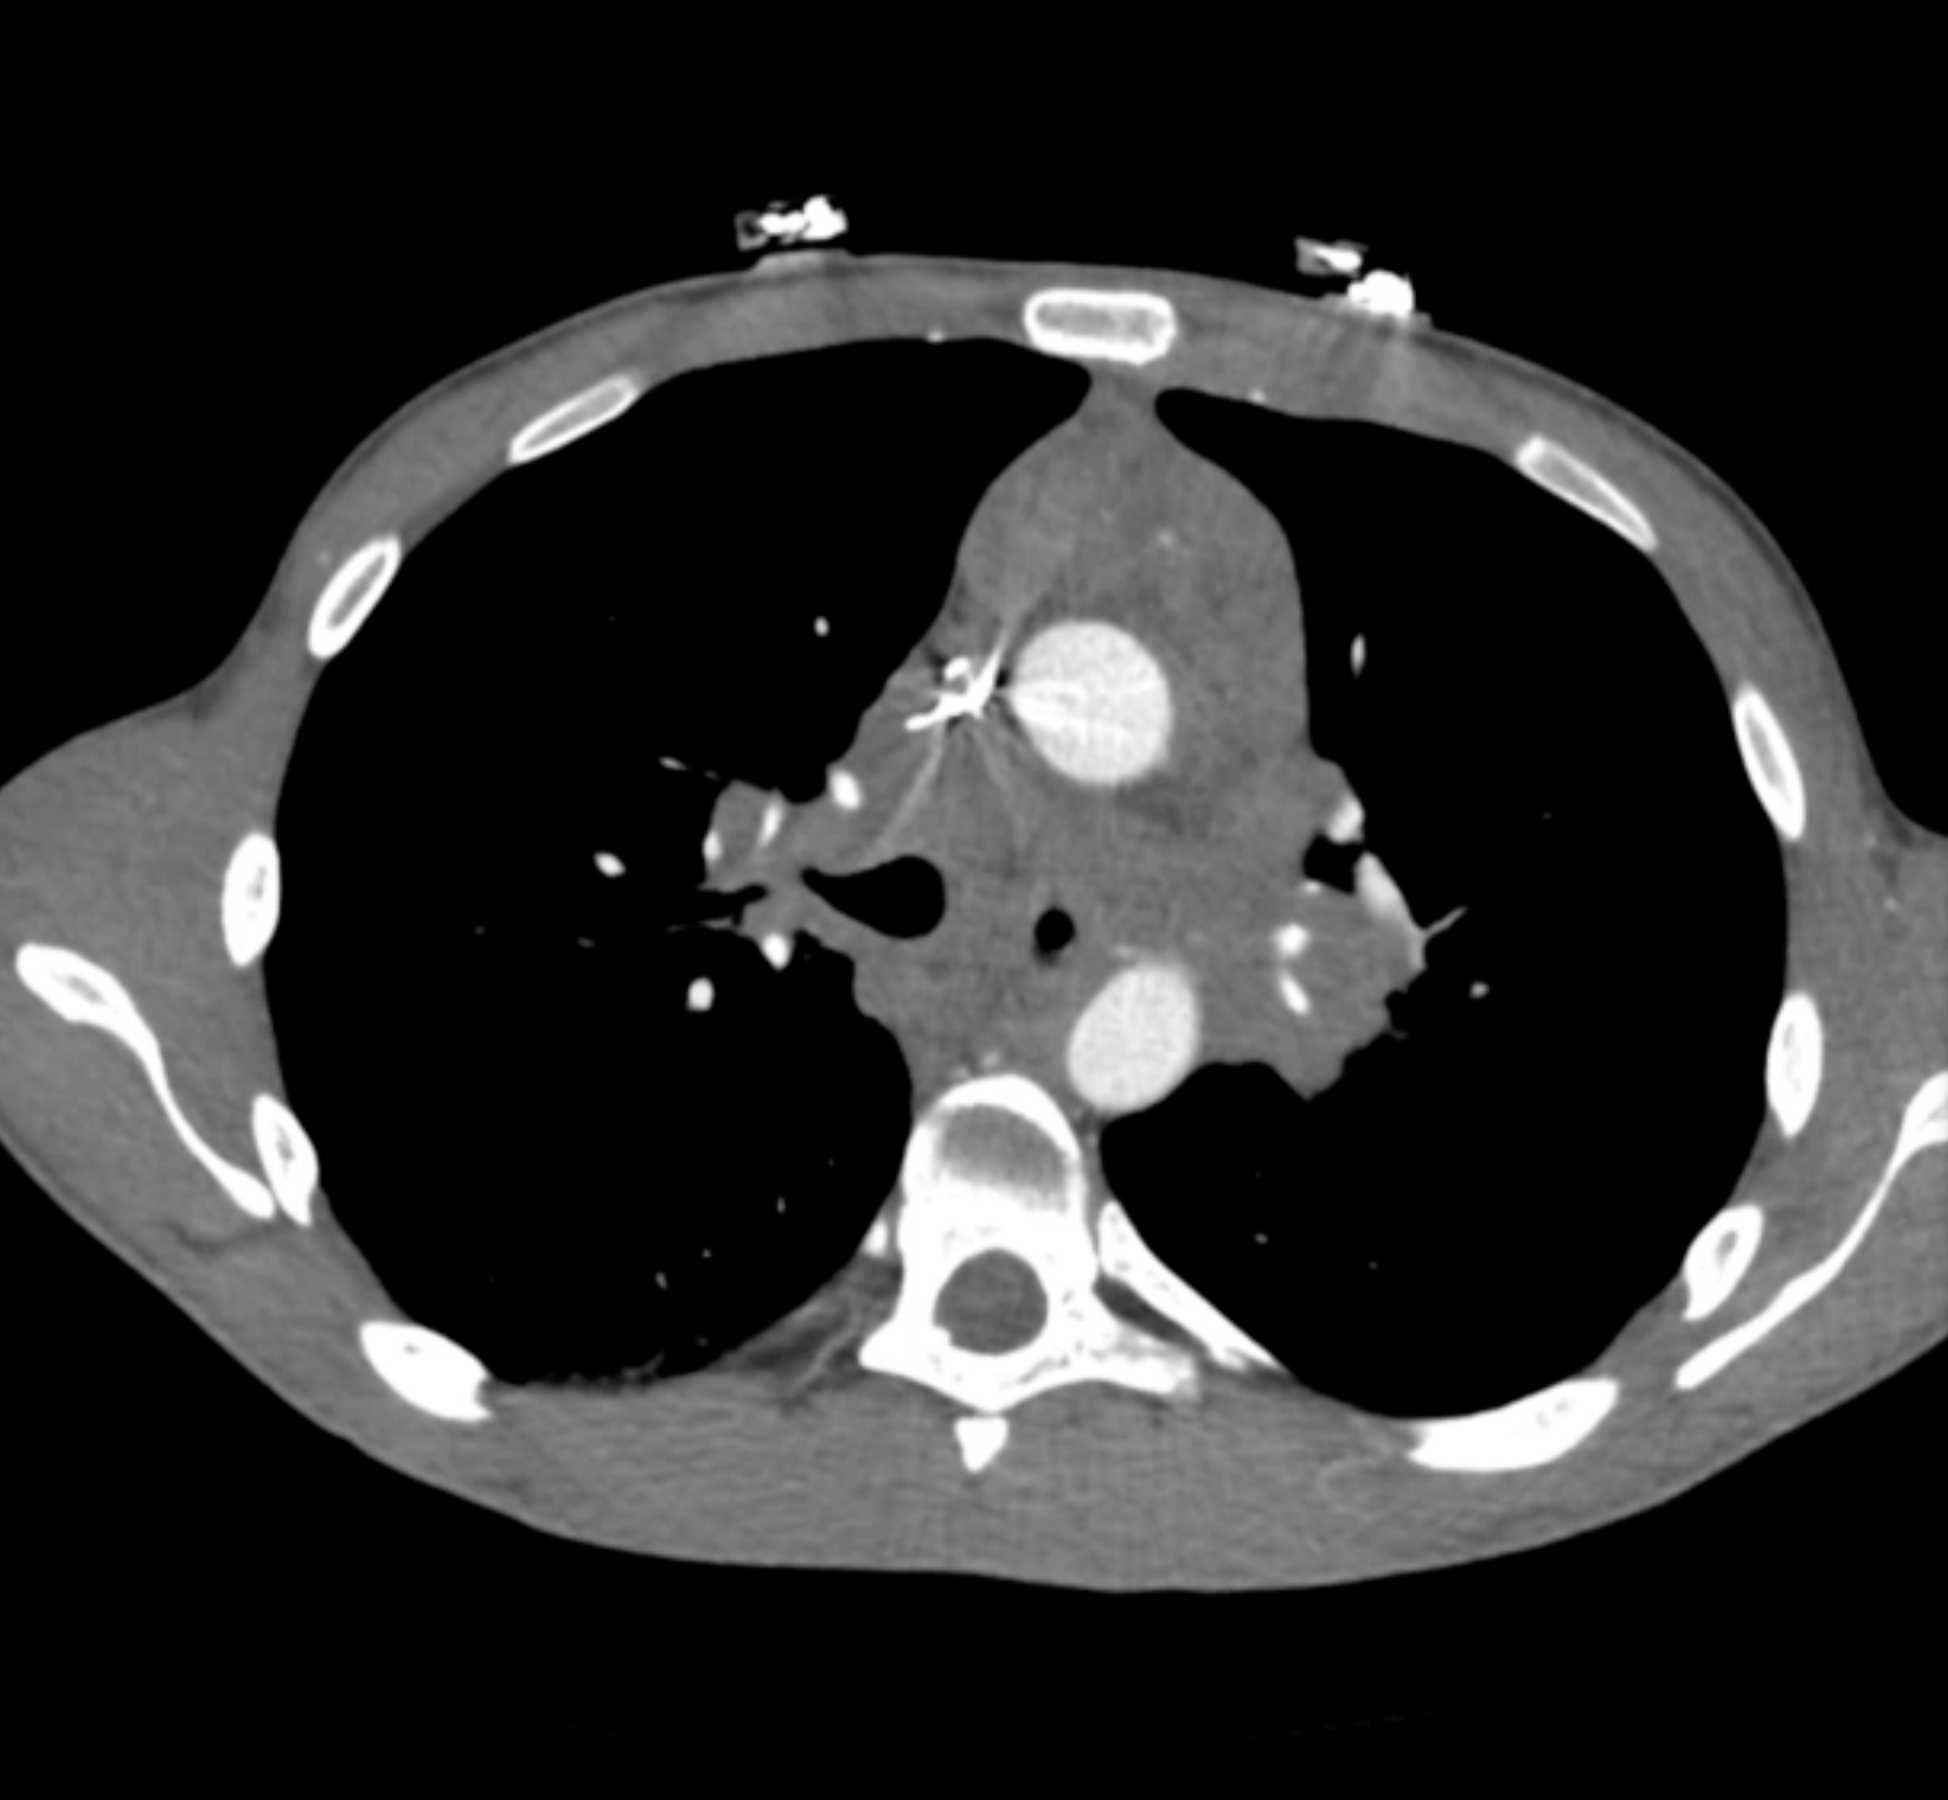

Large Cell Lymphoma